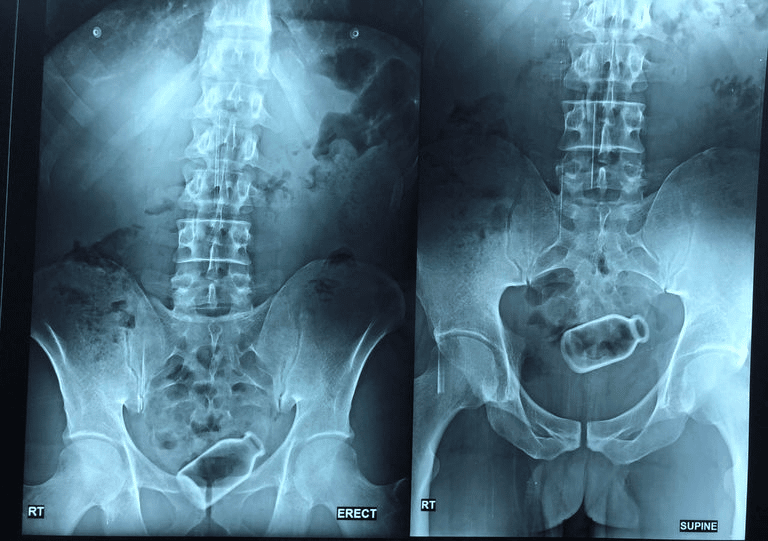

نجح فريق طبّي مصري، اليوم الجمعة، في استخراج زجاجة من قولون مريض، دخلت بسيناريو خيالي، واستقرت داخله لمدة أسبوعين.

ووفقًا لوسائل إعلامية مصرية، أدخل رجل (38 عامًا) في مدينة المنصورة بمحافظة الدقهلية، زجاجة إلى القولون عن طريق فتحة الشرج، حيث كان يعاني من إمساك مزمن، ونصحه أحد الأشخاص باستخدام الزجاجة لتوسيع فتحة الشرج وحل المشكلة.

وكشفت الدكتورة أسماء جميل، مدرس واستشاري الجهاز الهضمي والمناظير بجامعة المنصورة، عن إجراءات دقيقة لاستخراج الزجاجة، مؤكدة أنّ المريض عمل بنصيحة الشخص، وأثناء محاولته لتنفيذها، دخلت الزجاجة إلى القولون ولم يستطع استخراجها، ولم يخبر المريض أحدًا بذلك إلا أنّه بعد فترة أخبر شقيقه.

يعاني مشاكل نفسية

وأفادت في تصريحات لوسائل إعلام محلية مصرية، أن المريض يعاني من بعض المشاكل النفسية، وكان يشعر بالخوف من إخبار أحد بتلك المشكلة، واستغرقنا أسبوعين حتى نتمكن من إقناعه من إجراء تلك العملية لاستخراج الزجاجة وكان يرفض.

وأفادت أن المريض كان يخشى من العمليات، ورفض التخدير؛ خوفًا من الاستيقاظ أثناء العملية؛ حيث إنه ظن أنه سيستيقظ ويجد بطنه مفتوحة، أو أن يتم إزالة القولون.

وعن تفاصيل الجراحة، أكدت أن الزجاجة كانت مستقرة ولم تثقب في القولون، وكانت على بعد 20 سم من فتحة الشرج، وهذه مسافة بعيدة نسبيًّا، ومن الطبيعي عند وجود جسم غريب في القولون يكون قريبًا من فتحة الشرج، وعادة يتم استخراجه عن طريق الجراحة أو اليد.

وأفادت أنّه عن طريق الآلات والأجهزة الطبية، ودون جراحة، تمكنا من استخراج الزجاجة من قولون المريض في عملية استغرقت حوالي ساعة.